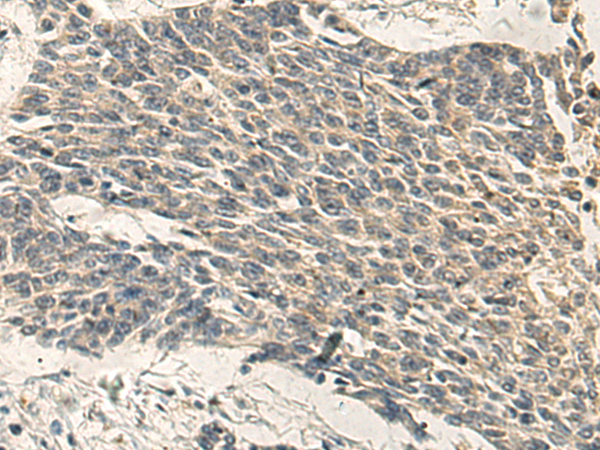

分类: 科研抗体货号: P13549别名: HAD; HCDH; HHF4; HADH1; SCHAD; HADHSC; MSCHAD应用: WB,IHC反应种属: Human, Mouse, Rat